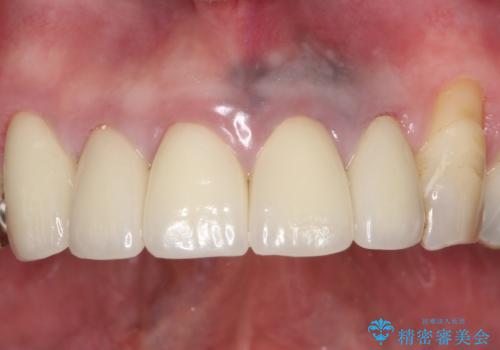

- 上の前歯の根元が黒くなっているので、再治療をしたいとのことで来院された患者様です。

レントゲンを撮影すると、適合不良のかぶせ物が装着されており、根の治療も不十分であることが確認されました。

適合不良のかぶせ物をすべて除去して、根の中の治療から再治療を行うこととなりました。

適合不良のかぶせ物が装着されていた歯は、内部がやはり虫歯になっていました。

かぶせ物だけではなく見えないところも、精密な治療をすることが重要となります。